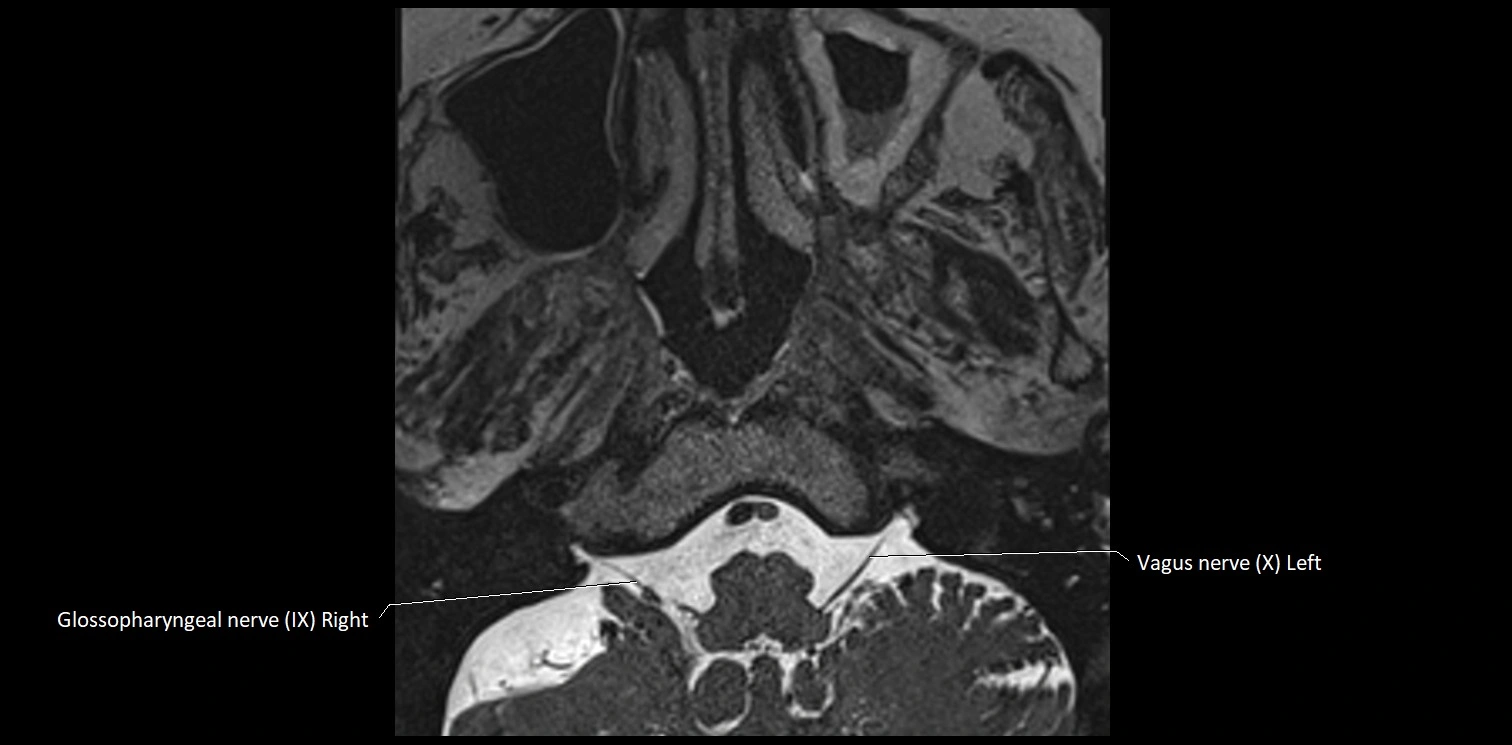

MRI images

image